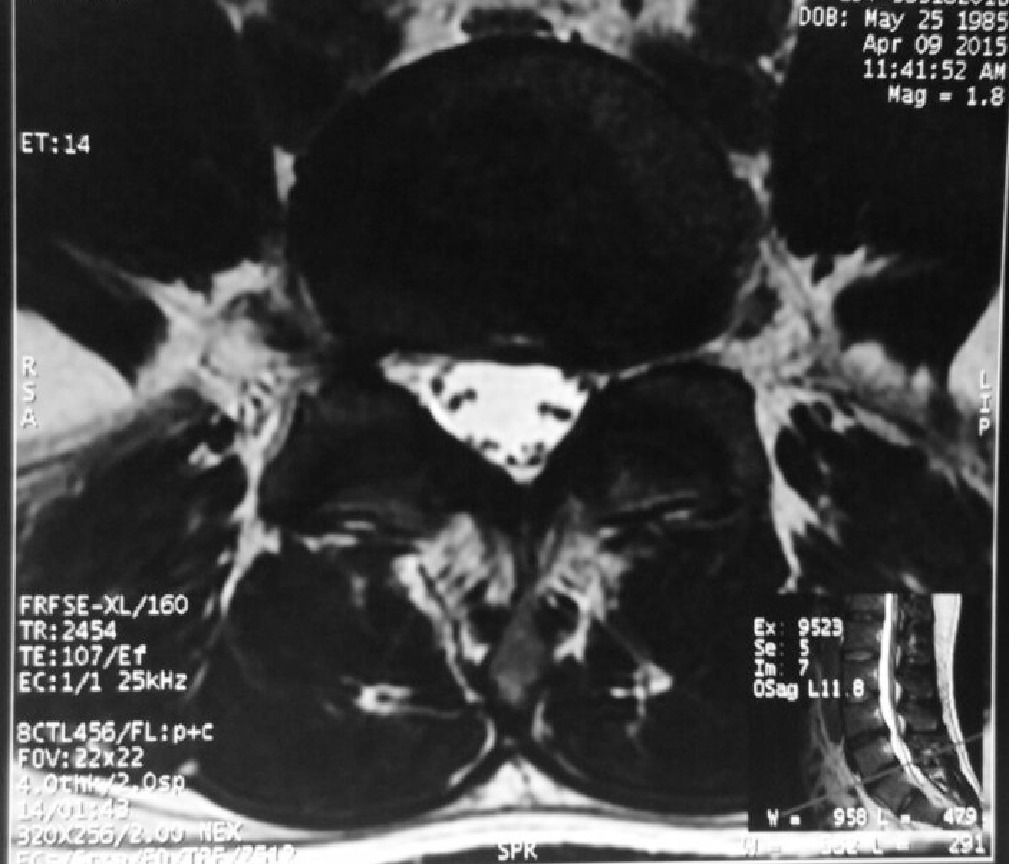

The same patient underwent a new MRI scan of his lumbar spine in 2015 for lower backache. There was no sciatica in his lower limbs.

The MRI showed resorption of the previous large left sided slipped disc.